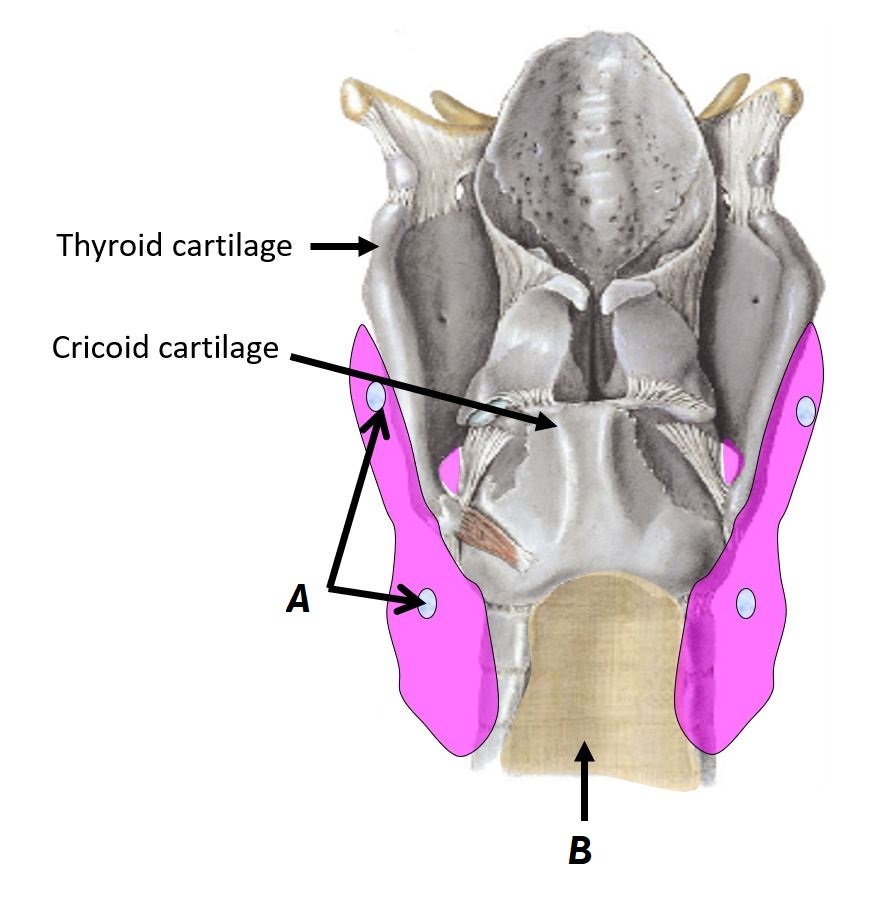

Name structures A and B

A - Thyroid cartilage

B - Cricoid cartilage

Name structures A and B

A - Parathyroid glands

B - Trachea

Name structures A and B

A - Thyroid cartilage

B - Cricoid cartilage